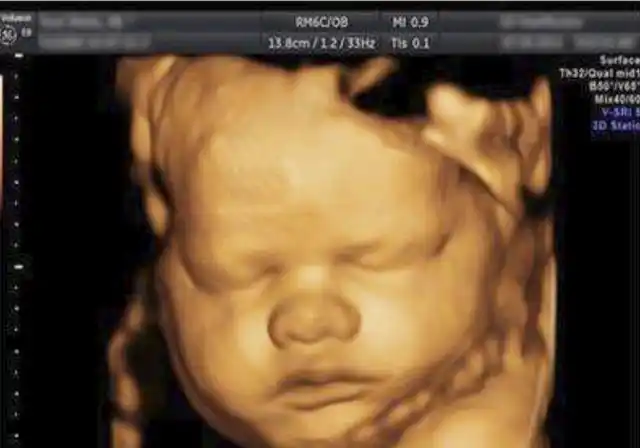

小猪先生兜儿晒孩子四维图大眼睛高鼻梁大嘴巴比小猪妹强多了

刚看到四维的时候我跟孩他爸都惊呆了,大鼻子,厚嘴唇,感觉还有点腭裂

胎儿的四维照片,跟实际相貌有区别吗?

四维通过,大眼睛高鼻梁酒窝女宝接走